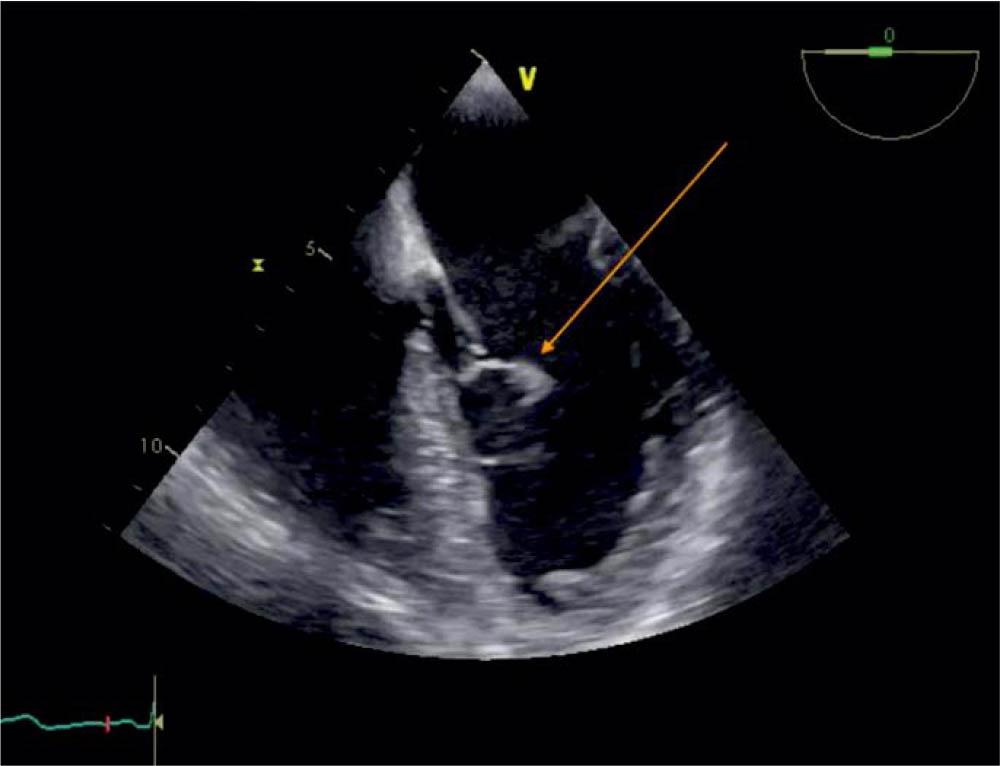

Figure 4